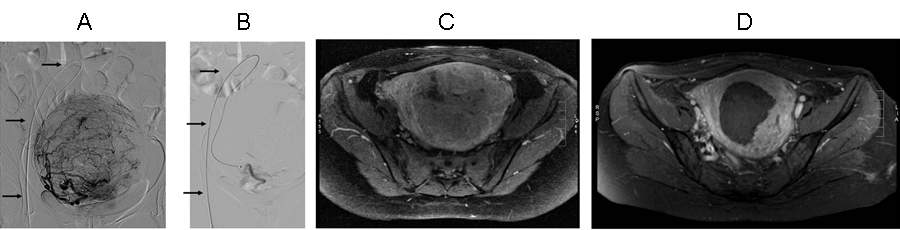

Figure 9. Uterine artery embolisation due to symptomatic fibroid. Panel A and B: angiography before (A) and after (B) embolisation; arrows point to the catheter. Panel C and D: T1 weighted, contrast enhanced axial MR image before (C, myometrium and fibroid are both enhancing) and 5 months after embolisation (D, myometrium is enhancing, fibroid is no longer enhancing contrast medium; fibroid is considerably smaller in size).

Uterus fibroids are among the most frequent benign tumors, it occurs upto 30% among the 35-55 year old females. However, it causes symptoms only in every 5th patient. Embolisation is indicated in symptomatic fibroids or symptomatic adenomyosis. Bilateral uterine artery embolisation elicits significant symptom reduction in 80-90% of the patients while the size of the fibroid is decreased by 20-25% in diameter and by 50-60% in volume at 6 months. Due to the embolisation, hysterectomy is not necessary in the vast majority of the patients.